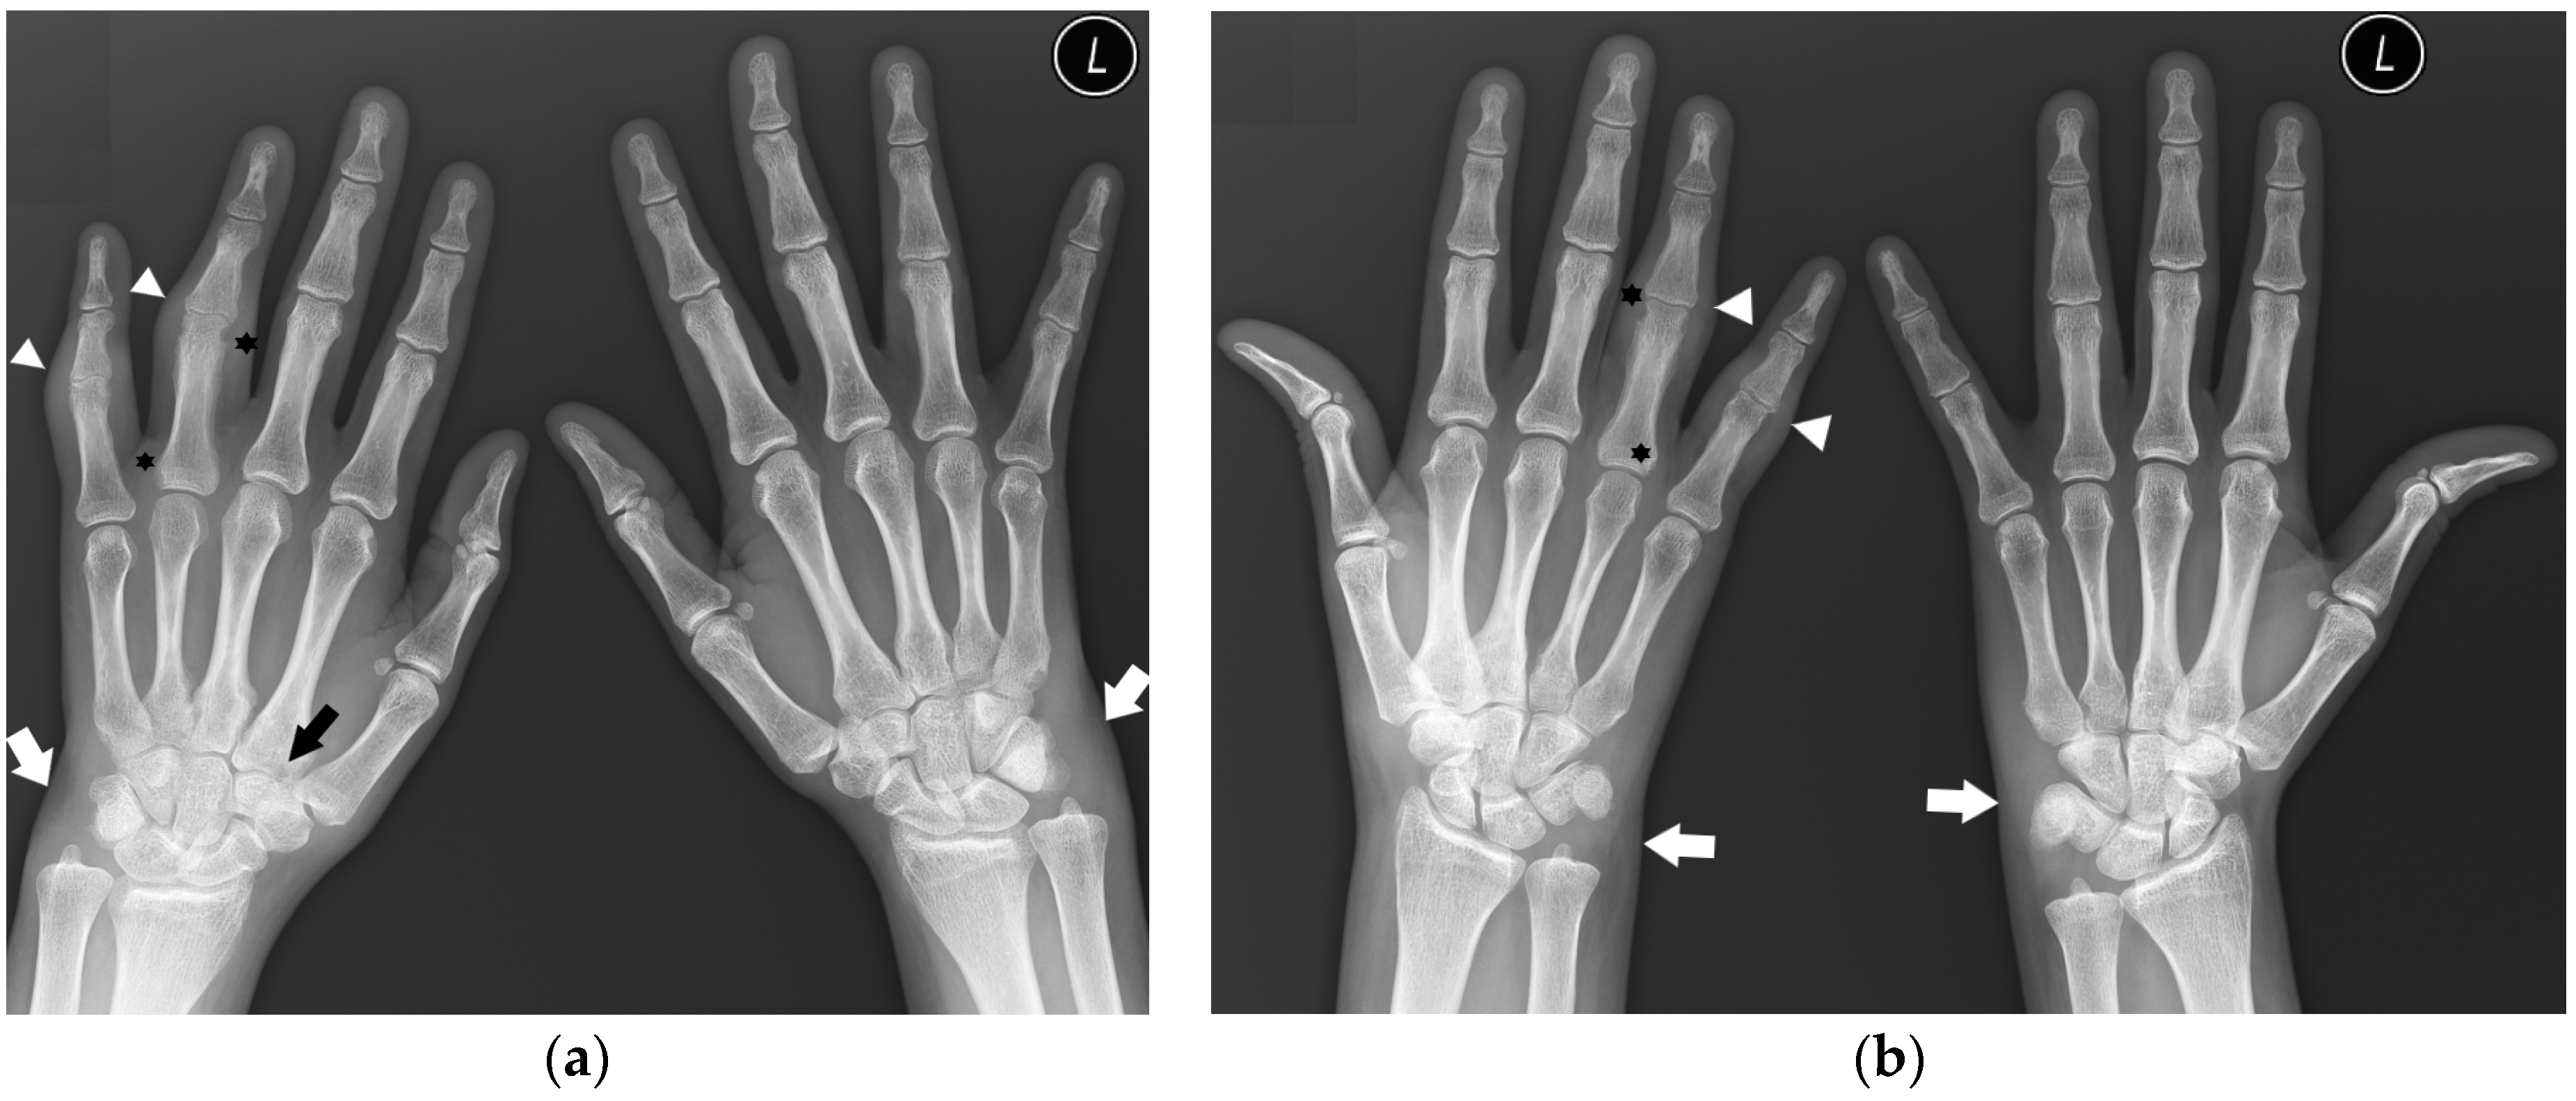

The distribution of involved joints in RA is widely described in the literature as “bilateral and symmetrical” [1,16]; however, the disease may begin as unilateral and asymmetric arthritis [15] (Figure 1).

Figure 1.

A 40-year-old female with early asymmetric seropositive rheumatoid arthritis (RA). (a) Posterior–anterior (PA) radiographs of bilateral hands show narrowing of the left radiocarpal joint (RCJ) and carpo-metatacarpal (CMC) joints (black arrows). Note the bone cyst in the left second metacarpal head and narrowing of the second metacarpophalangeal joint (MCP) (white arrow). (b) PA radiograph of the bilateral hands of the same patient, 13 years later, showed progression of the disease with increased juxta-articular osteoporosis. Note the erosive bone changes, advanced destructive changes, and joint narrowing in the RCJ and CMC joints. There are less advanced changes on the right side with joint space narrowing and bone cysts in the wrist (black arrow). Note proliferative osteoarthritic changes in left distal radioulnar joint (DRUJ) and bilateral first MCP and interphalangeal joints (white arrows). There is subluxation of the right thumb interphalangeal (IP) joint (star).